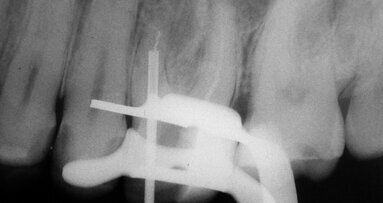

La fracture d’un instrument endocanalaire au cours du traitement endodontique est une situation fréquente. Selon les études, le risque ...